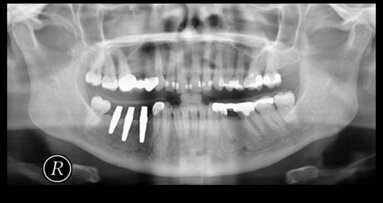

Jeddah – In der Implantologie entscheidet nicht nur die Präzision der Chirurgie. Auch die Kontrolle von Infektionen gehört zu den zentralen Voraussetzungen für langlebigen Zahnersatz und stabile Implantate. Kommt es zu mikrobieller Besiedlung, können Erkrankungen wie Prothesenstomatitis oder Periimplantitis entstehen. Üblicherweise werden dafür synthetische Desinfektionsmittel eingesetzt, allen voran Chlorhexidin. Dessen Wirksamkeit ist belegt, doch Nebenwirkungen wie Schleimhautirritationen, zelltoxische Effekte oder die Förderung resistenter Keime haben den Blick auf Alternativen gelenkt.

Die im Journal of Exploratory Research in Pharmacology veröffentlichte Übersichtsarbeit von Manar Hamed Almehyawi und Kollegen fasst den Stand der Forschung zu natürlichen Desinfektionsmitteln in der Prothetik und Implantologie zusammen. Analysiert wurden pflanzliche, tierische und mineralische Substanzen, die in vitro und in vivo antimikrobielle Effekte gezeigt haben. Im pflanzlichen Bereich stehen Clove oil mit dem Wirkstoff Eugenol, Grüntee-Extrakte mit Epigallocatechingallat, Teebaumöl, Neem, Aloe vera oder Zimt im Fokus. Sie wirken durch die Zerstörung bakterieller Zellwände, die Hemmung von Enzymen, die Beeinflussung von Quorum-Sensing-Prozessen und die Unterdrückung von Biofilmen. Tierische Produkte wie Propolis oder Honig zeichnen sich durch antimikrobielle und entzündungshemmende Eigenschaften aus. Auch Substanzen wie Sericin oder Bienengift werden diskutiert. Mineralische und mikrobielle Produkte, etwa Tonminerale, Zeolithe oder Bakteriozine wie Nisin, ergänzen das Spektrum.

Die Studie beschreibt Anwendungen, die von pflanzlichen Mundspülungen und Gelen über die Reduktion von Candida-Belägen auf Prothesen bis hin zur Integration natürlicher Substanzen in Prothesenmaterialien reichen. Auch antibakterielle Beschichtungen von Implantatoberflächen, etwa mit Totarol, werden genannt. Damit verbinden die Autoren eine Reihe von Vorteilen wie gute Biokompatibilität, geringere Toxizität und ökologische Nachhaltigkeit. Grenzen ergeben sich durch die variierende Zusammensetzung der Substanzen, fehlende Standardisierung und bislang eingeschränkte klinische Evidenz. Zugelassen sind die Präparate derzeit nicht, sondern meist nur als frei verkäufliche Produkte erhältlich. Die Autoren kommen zu dem Schluss, dass natürliche Desinfektionsmittel ein hohes Potenzial für den Einsatz in Prothetik und Implantologie besitzen. Voraussetzung für eine breite klinische Anwendung seien jedoch standardisierte Herstellungs- und Prüfverfahren sowie belastbare klinische Studien.